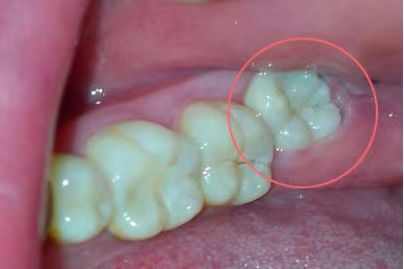

第二位患者同樣姓張,但他在25歲的年紀(jì),卻已經(jīng)被智齒疼痛折磨了2年多了。小張自述,自己的智齒疼,并不是“疼起來要人命”的那種,所以才一拖再拖。但近期,小張的下頜右側(cè)牙齦反復(fù)長膿包,因擔(dān)心病變擴(kuò)大,才終于鼓足勇氣走進(jìn)了口腔科。醫(yī)師在檢查小張口內(nèi)情況時(shí)看到,該患者下頜右側(cè)第二磨牙牙冠表面完整,但在頰側(cè)牙齦位置處,可見約5mm直徑的膿包,膿包下,一顆牙冠傾斜部分微微露出的智齒隱約可見,而這兩顆牙齒之間,竟有著大量嵌塞的食物,已然形成齲洞!并且第二磨牙周圍骨質(zhì)被破壞嚴(yán)重,牙齒已經(jīng)是“懸浮”在牙槽窩內(nèi),這顆看似完整的牙齒因?yàn)橹驱X給予的阻力和齲洞的存在,其實(shí)已經(jīng)不具有保留價(jià)值了,只能和智齒一起被連根拔除。